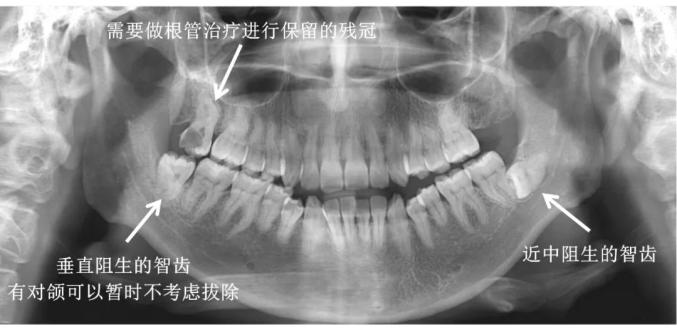

如果龋齿已经进展到牙神经发炎(不可逆牙髓炎),甚至根尖周炎,则需要做根管治疗,控制炎症,之后再做修复。

一般来说,如果智齿长的位置比较端正,也没有影响到其他牙齿,不会对口腔健康造成危害,没有疼痛不适感,那或许就可以不拔。